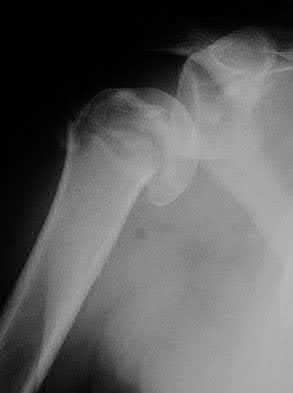

A 70-year-old woman falls down a flight of stairs and sustains the injury shown in Figures A and B to her dominant upper extremity. She lives alone and has no other medical history. Which of the following surgical options is best to minimize complications for this fracture pattern?

This patient has a complex proximal humerus fracture with metaphyseal comminution and poor bone stock. Cemented reverse total shoulder arthroplasty (rTSA) using a long stem prosthesis and tuberosity repair is indicated.

Proximal humerus fragility fractures are hard to treat because of comminution and poor bone stock. AVN is common with glenohumeral fracture-dislocation. Hemiarthroplasty (and standard total shoulder arthroplasty, TSA) is unreliable because of dependence on tuberosity healing. rTSA is recommended for fractures in patients >70 years with severely comminuted fractures, high likelihood of head AVN, and poor tuberosity bone quality (osteoporosis or comminution).

Bufquin et al. retrospectively reviewed the use of rTSA for treatment of 43 patients with 3- and 4-part proximal humerus fractures. They found satisfactory elevation (97°), ER in abduction (30°), constant scores (44) and modified Constant scores (66%). Complications included calcification (90%), tuberosity displacement (53%) and scapular notching (25%). They concluded that rTSA was a good procedure because it provides pain relief and easier functional recovery in spite of failed tuberosity healing.

Anakwenze et al. systematically reviewed acute proximal humerus fractures. Frequency weighted range of motion was flexion 122°, abduction 97°, ER at neutral 18°. Tuberosity repair yielded higher ER compared to no repair.

Scapular notching was the most common complication (32%). They concluded that rTSA patients tended to be elderly women with 4-part fractures, had good pain control but residual dysfunction.

Jobin et al. reviewed rTSA for management of proximal humerus 3- and 4-part fractures. They note >50% of cases have tuberosity resorption. They recommend repairing the greater tuberosity to restore infraspinatus/teres minor function which improves external rotation strength. Greater tuberosity malunion is not a result of secondary displacement, but rather, from intraoperative malreduction. Lesser tuberosity repair should be performed if there is significant bone loss or intraoperative anterior instability.

Figures A and B are AP radiograph and 3D reformatted CT scan showing comminuted proximal humerus fracture dislocation. Illustration A shows rTSA performed with distal cementation of a long stem prosthesis and cerclage fixation of the proximal shaft and the tuberosity fragments.

Incorrect Answers:

Answer 1: ORIF has potential complications of screw cut out, AVN, fracture collapse, tuberosity resorption and loss of fixation. The risk of AVN (and resultant screw cut out) is high because of comminuted fracture-dislocation. Answer 2: Cementing is indicated because metaphyseal fracture bone loss compromises stem fixation.

Answer 3: Greater tuberosity repair improves external rotation strength. Lesser tuberosity repair adds to anterior stability.

Answer 5: Proximal humeral replacement is only necessary for tumor or unreconstructable fractures. They have poorer outcomes because of loss of rotator cuff function.